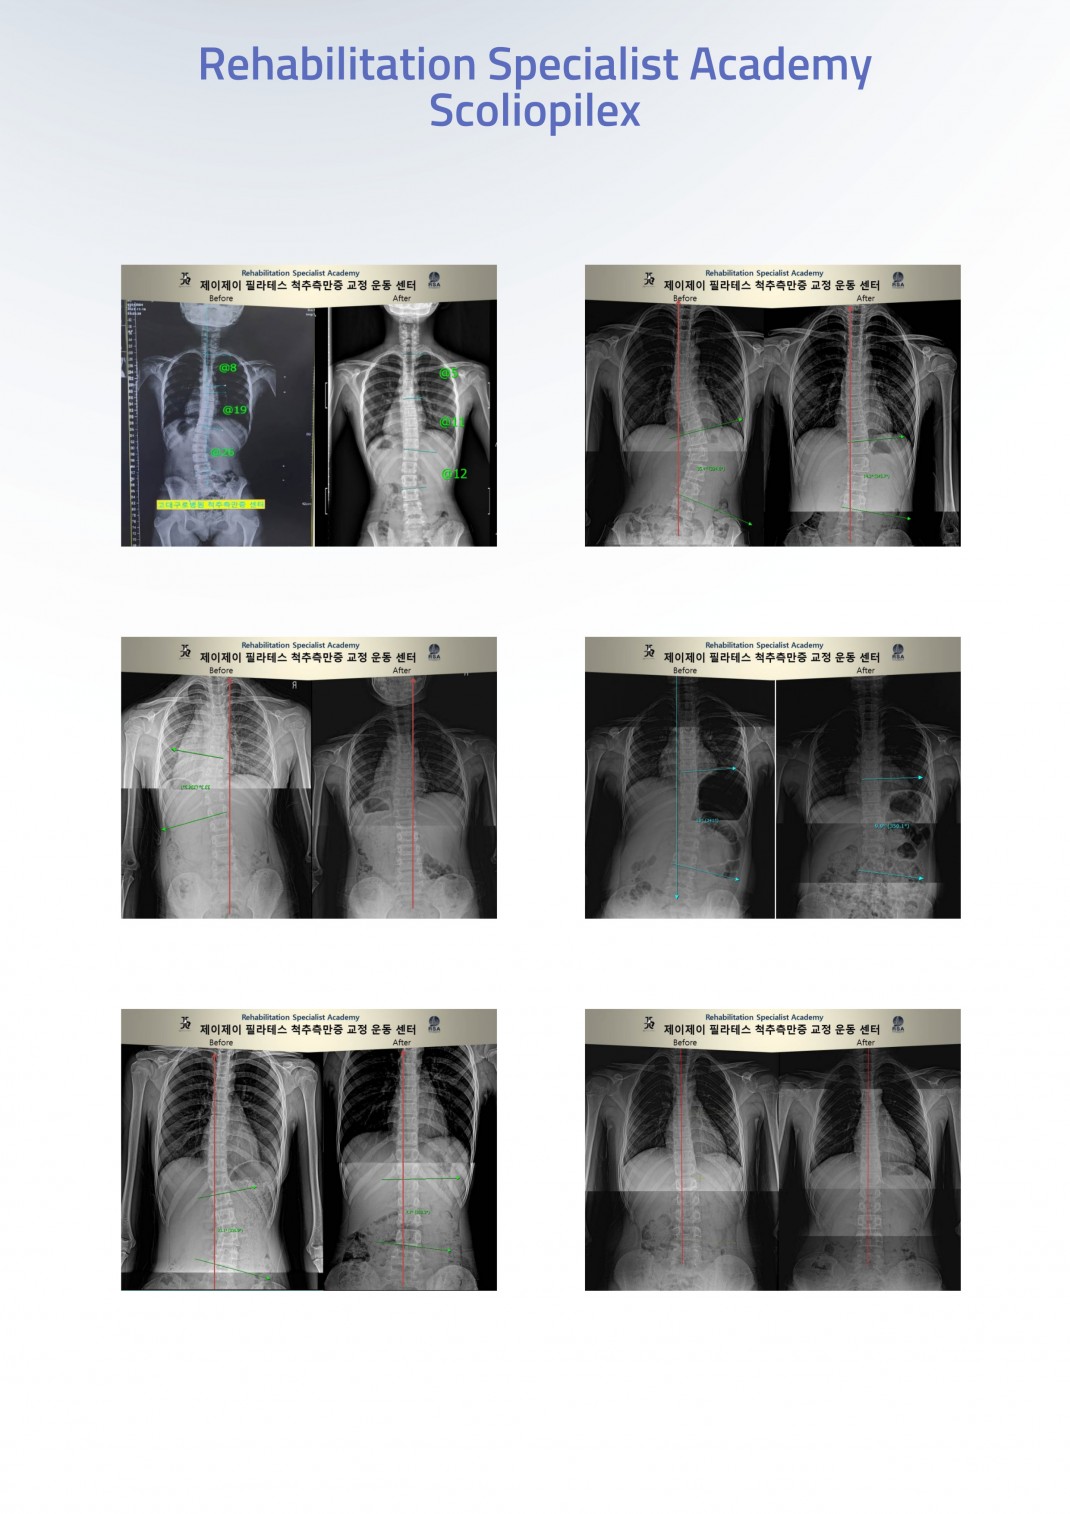

RSA 운동전문가를 위한 체형 및 척추측만증 교정운동

One Day Class(부산/경남)

Case Workshop

실제 척추 측만증 회원을 모시고 평가 및 운동

척추측만증의 이론부터 필라테스 기반 교정 운동까지

250명 이상의 교정 경험을 가진 전문가와 함께,

실제 케이스 회원분을 모시고

외형평가

X-ray 평가

운동 설정

운동 적용

까지 All-in-one

교정운동의 기준을 배우고 싶은 분,

척추측만증 케이스 접근을 배우고 싶은 분,

실제 효과를 눈으로 확인하고 싶은 분